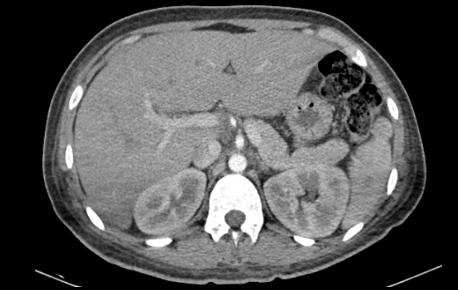

- Diagnostic imaging of the chest and abdomen revealed no additional abnormalities.